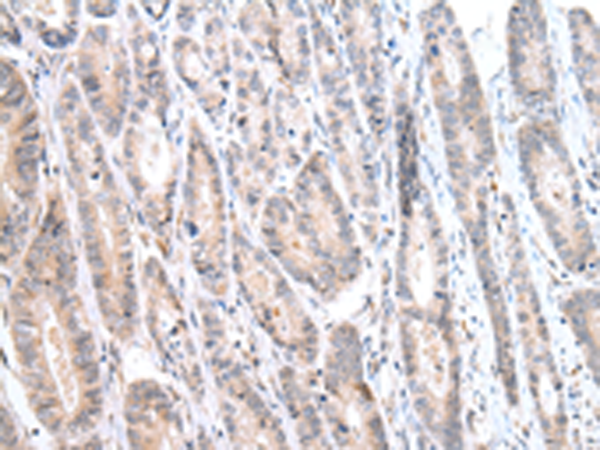

分类: 科研抗体货号: P12492别名: CR; CAL2; CAB29应用: WB,IHC反应种属: Human, Mouse, Rat